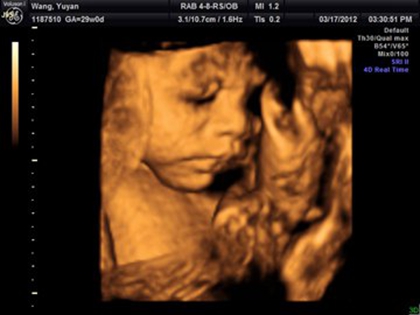

一张四维图助你识别女宝宝特征,最明显的还是三条线

四维彩超是一种排畸检查,一般在女性怀孕20~26周的时候就要做这项检查。很多人对胎儿性别比较好奇,就会通过这项检查来辨别胎儿性别。一般如果四维图上出现三条白线,双顶..

四维女宝宝三条线特征图片长什么样,四维男宝也有三条线吗?

网上流传着四维彩超的报告上如果是有三条线就是女孩,而如果没有三条就是男孩,那么四维女宝宝三条线特征图片长什么样呢,四维男宝也有三条线吗?四维女宝宝三条线特征图片..